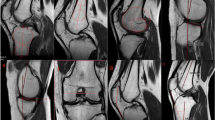

CT scans were performed postoperatively, as a routine examination when possible (initially for the evaluation of the positioning of femoral and tibial tunnels after ACL reconstruction), and analyzed in our Institutional Picture Archiving and Communications System (PACS, Centricity, GE Healthcare, Waukesha, WI). All examinations were carried out in the same institutional radiology department. The images were acquired in axial sections from which reconstructions in the coronal and sagittal planes were carried out by an experienced orthopaedic surgeon. No postoperative artifacts degraded the quality of CT scans. The distal femoral and proximal tibial epiphyseal regions were analyzed in three dimensions. The tests were carried out on CR-Brillance equipment CT 64 using a volume acquisition technique without injection (thickness 0.67 mm; increment 0.33 mm; 140 kVp; MAs 300 ; high resolution; no automatic dose modulation; collimation 16 × 0.625 mm; pitch 0.435; rotation 0.75 s/rev; FOV 250 mm).

All images were analyzed using the image processing software (Philips® Intellispace Portal 7.0, Haifa, Israel) after import in DICOM format. Image processing was done in the CT Viewer in MPR mode, with double-obliquity image processing techniques. Treatment of the acquisitions was done after positioning of the tibia in three dimensions (Fig. 1): an axial plane passing through the center of the medial (point A) and lateral (point B) tibial plateaus (plane 1) controlling rotation of the tibia, a coronal plane including the longitudinal anatomical axis (plane 2), and a sagittal plane through the proximal tibial anatomic axis (PTAA, plane 3). Measurements of the distal femoral epiphysis were made with respect to the tibia-defined cutting planes.

The tibial slope evaluation was based on the radiological work of Bonnin et al. [7] and the CT scan evaluation of Kessler et al. [20], using the proximal tibial anatomic axis (PTAA), which has been shown to be strongly correlated to the mechanical tibial axis [5, 41, 44] and has been used by the American Knee Society [8]. The first step was to determine the PTAA by connecting two equidistant points of the anterior and posterior tibial cortices, one just under the anterior tibial tuberosity and a second 10 cm more distal. The wide scan allowed visualization of the entire anterior and posterior cortices on the same image, creating a real three-dimensional reconstruction. The previously defined PTAA was then applied to both the medial and lateral tibial plateaus on a mid-sagittal section (Fig. 2). The wide scanning method provided visualization of the entire bone relief on the same image by superimposing multiple adjacent cuts on both sides of the sagittal plane passing through the center of each plateau.

Medial tibial slope (MTS) was defined by the angle formed between the PTAA and the line joining the most proximal points of the anterior and posterior margins of the upper medial tibial plateau (Fig. 3). The value of the posterior slope corresponded to the difference between the angle obtained and the perpendicular to the PTAA. A posterior inclination was assigned a positive value, while an anterior inclination was assigned a negative value, according to convention [7, 9].

The same methodology was reproduced for the lateral compartment. The angle formed by the line joining the most anterior and posterior point of the subchondral surface and the perpendicular to the PTAA determined the lateral tibial slope (Fig. 4).